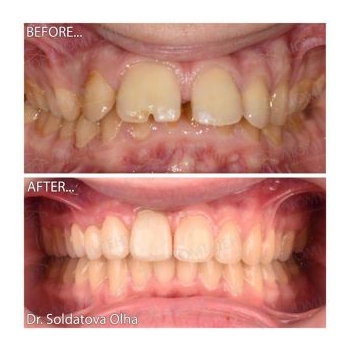

Выше можно увидеть фото до и после выравнивания неправильного прикуса у ортодонта пациентам «Люми-Дент».

Другие примеры работ наших докторов, исправление прикуса зубов в Киеве, фото до и после:

- На этой странице, и в разделах каждой отдельной услуги выравнивания зубов - можно увидеть много фото прикуса до и после лечения неправильного зубного смыкания у подростков, людей в возрасте. Фото до и после исправления прикуса в Киеве брекетами, пластинками, капами, трейнерами;